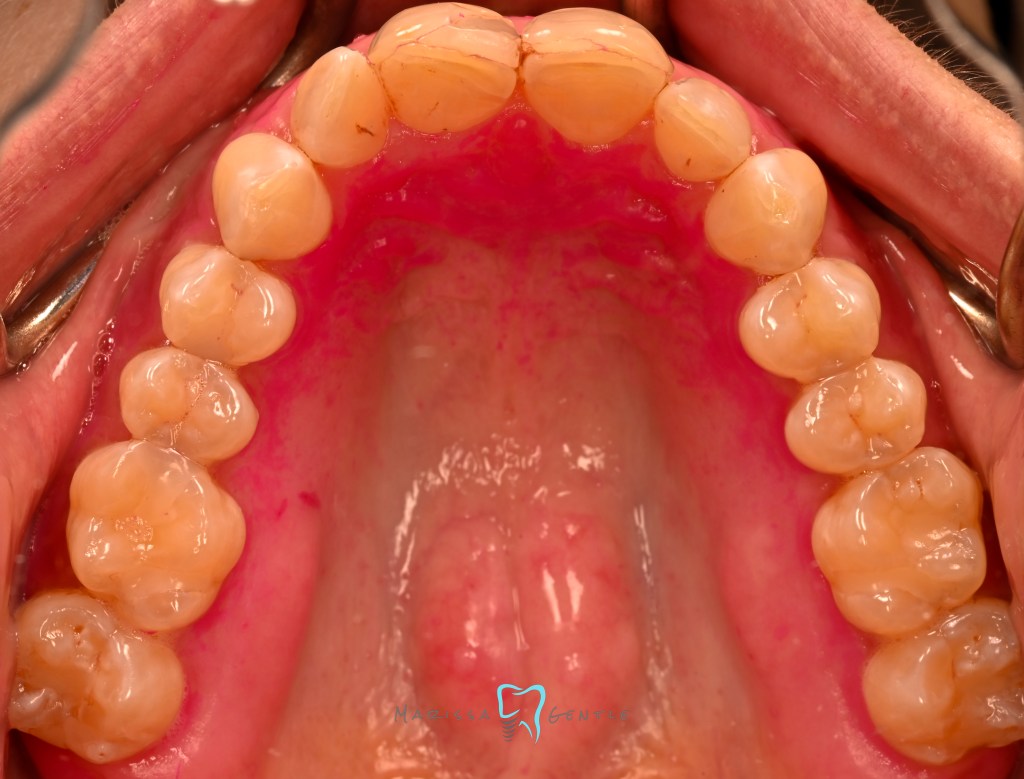

Patient presented with esthetic concern, composite veneers were placed 3 years prior. Patient’s chief complaint is twisted #7, thickness of the composite veneers and now chipping. The veneers were placed initially due to Enamel hypoplasia. Clinically relevant information: the patient wears a mandibular advancement device as treatment for sleep apnea, malocclusion noted edge to edge. Zirconia crowns planned #7-10

Current composite veneers are defective and caries are clinically present